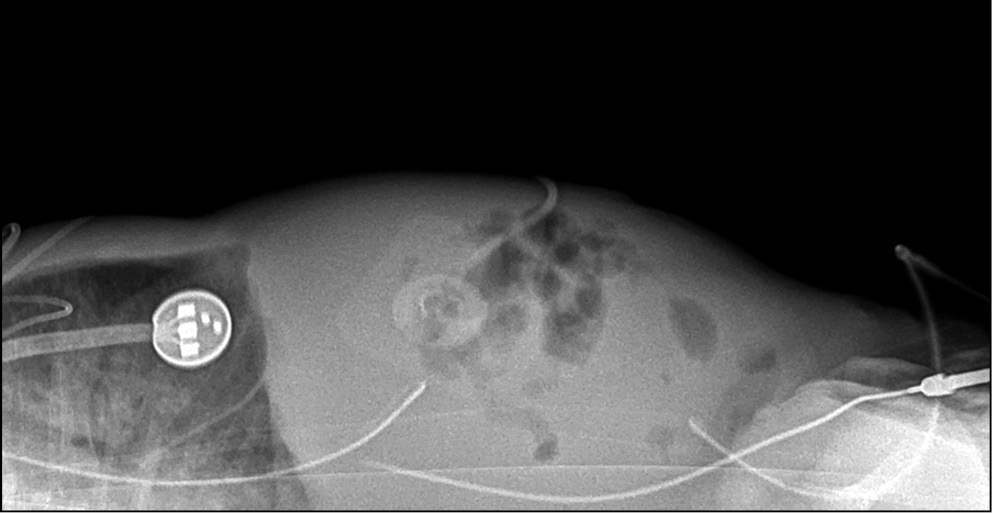

При невозможности вертикализации пациента для диагностики наличия свободного газа в брюшной полости возможно выполнение исследования в боковой проекции в положении лежа на спине (рис. 6).

Рис. 6. Рентгенограмма органов брюшной полости в боковой проекции. Исследование выполнено при помощи микрофокусного рентгеновского аппарата.

Fig. 6. Abdomens radiograph in lateral view. Microfocus X-ray device.